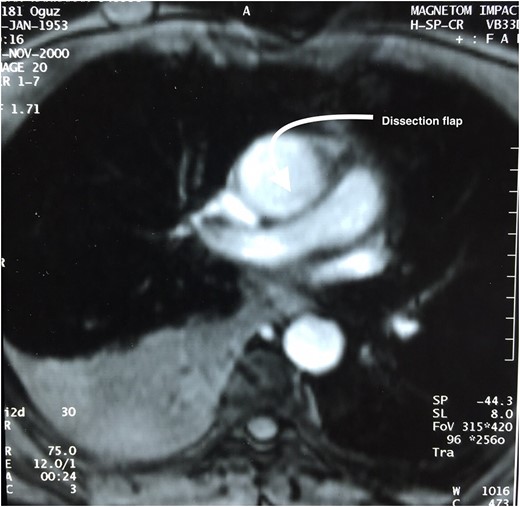

After observing such unexpected case (resembling type II aortic dissection) on surgery a patient was then questioned for further details on his medical history. Fifteen years ago, he was presented emergently to a cardiologist with chest pain, palpitation and sweating. On physical examination, he was hypotensive with sinus tachycardia. Both echocardiography and thorax magnetic resonance (MR) revealed pericardial effusion on posterior side of the heart (hemopericardium) with dissection flap (Fig. 3). His follow-up period was uneventful and he was then discharged from hospital with medical therapy, Echocardiography control (every 6 months) and thorax CT control (every 1 year). The last thorax CT (that we took in our clinic did not demostrate dissection flap (Fig. 1). Both imagings of Figs 1 and 3 were avaluated under the same radyologic level for accuracy.